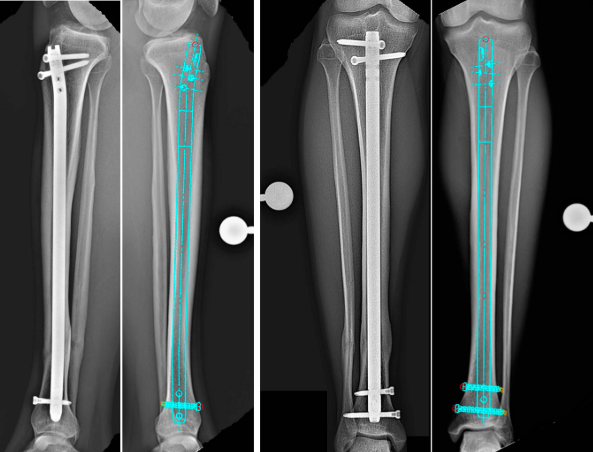

(Slika: Diagram zloma tibialne gredi)

* Položaj vodilne žice: Distalni konec vodilne žice naj bo sredinsko postavljen v sklepu gležnja, približno 1 cm proksimalno od tibialne ploščice. Potrdite položaj z AP in lateralno fluoroskopijo.

* Standard: Vodilni žični vodnik mora biti središčen 1 cm proksimalno od sklepa gležnja (potrjeno na AP in lateralni sliki).